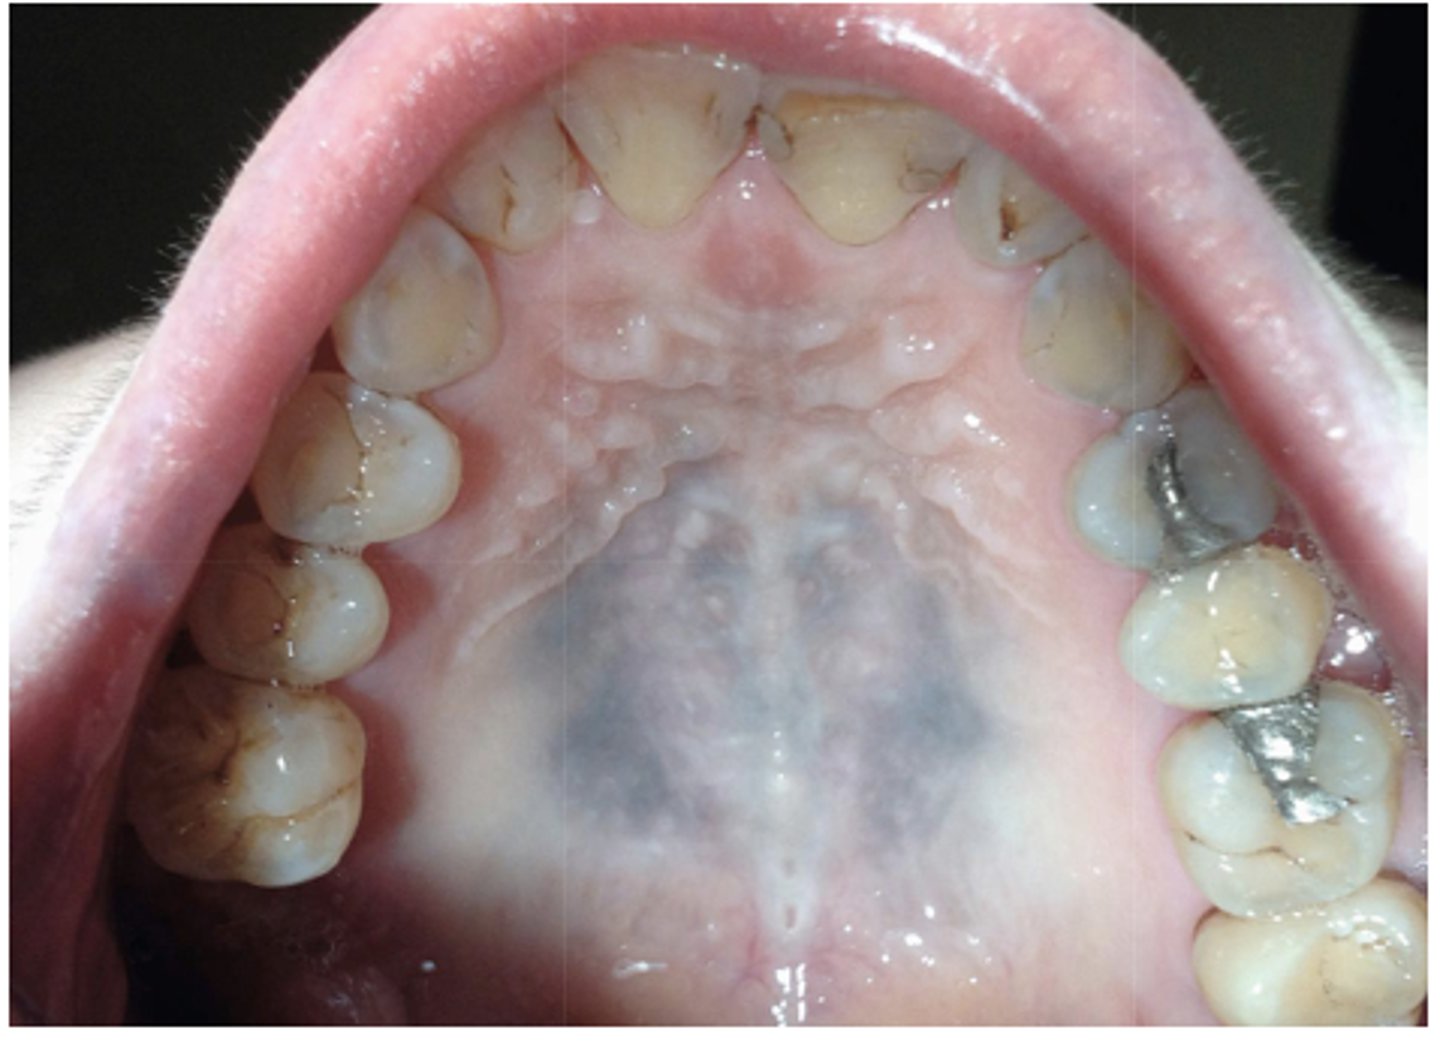

What type of pigmented lesion?

medication-induced pigmentation (typically palatal mucosa)

- Rare acquired pigmented lesion(s) of rapid onset

- Reactive?

- May reach several cm in size

oral melanoacanthosis (a.k.a. oral melanoacanthoma)

Oral Melanoacanthosis has a predilection for which ethnic group and which gender?

African American females

Oral Melanoacanthosis usually appears at which age?

3rd-4th decades

What is the differential diagnosis?

45 year-old African American female presented with this asymptomatic lesion for 2 months.

oral melanoacanthosis